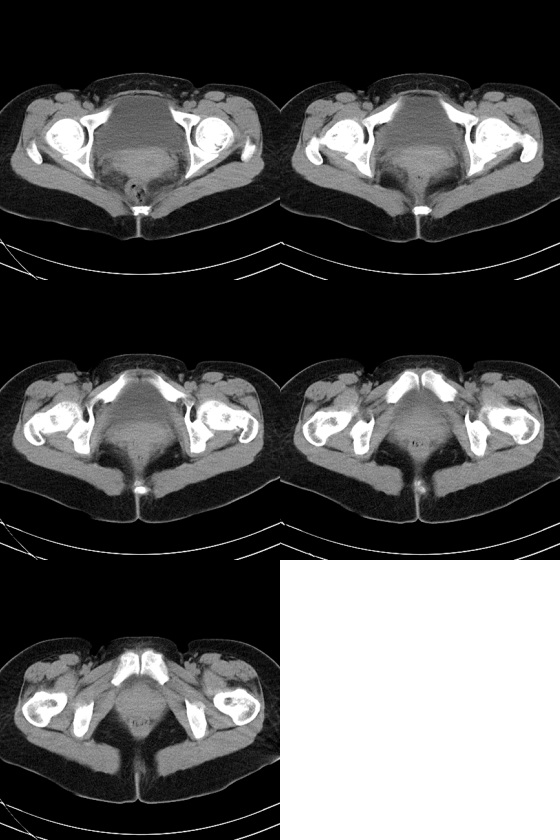

47岁女性,下腹部疼痛伴发热(38度)半月。b超提示宫底见3.0cm弱回声团块,边界清楚,形态规则,左侧附件区见不规则形态杂乱回声团块,其内可见液性暗区。b超同时提示肝脏见多个1.5cm的占位性病变。患者不同意做增强扫描。

1)左侧附件区囊实性占位性病变,性质待定;建议行进一步检查。2)子宫肌瘤?3)盆腔积液。

左侧附件区囊实性占位性病变,囊腺瘤或癌。

左侧附件区囊实性占位性病变,囊腺瘤或癌不排除!

1、考虑左侧卵巢癌并肝转移(依据:左侧附件区囊实性包块,盆腔有积液,肝脏有多个占位),当然没有增强只是提示一种可能性。

2、病人有发烧,又不能排除左侧输卵管感染性病变,如病人不增强那就抗炎治疗后复查有助诊断。